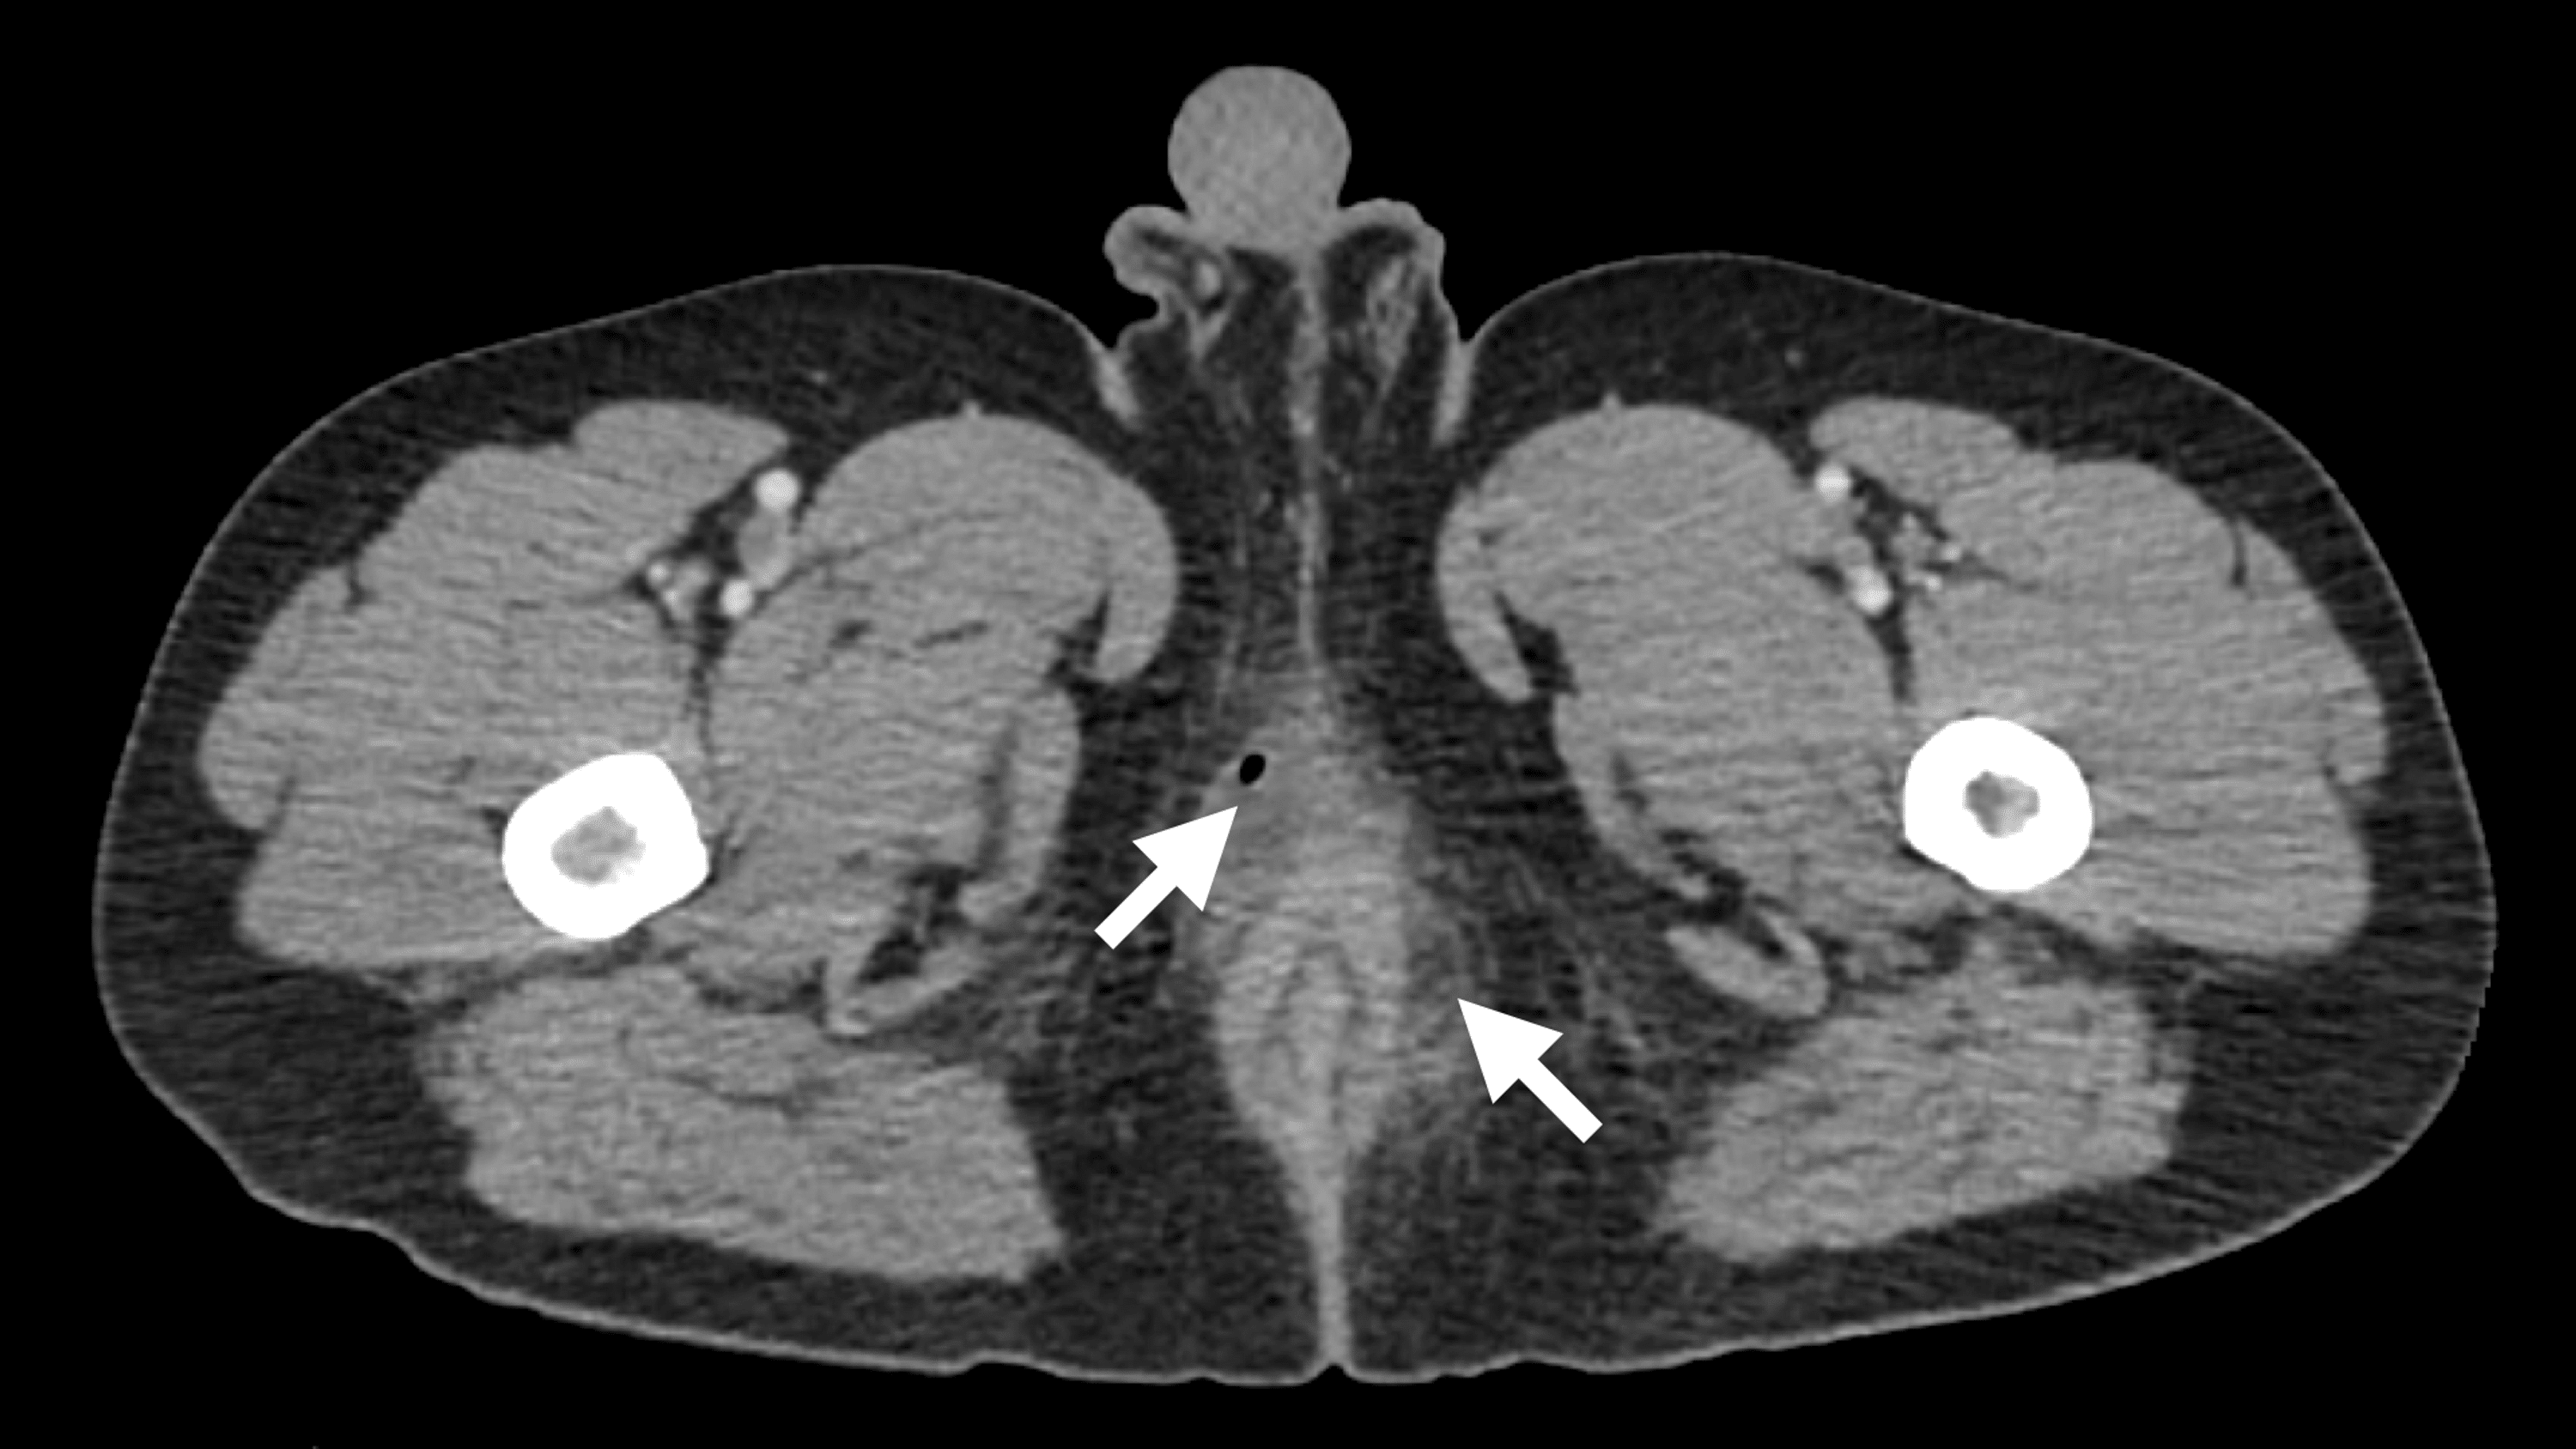

(PDF) Perianal Abscess Following Excisional Hemorrhoidectomy in an

From www.cureus.com

(PDF) Perianal Abscess Following Excisional Hemorrhoidectomy in an Abscess Excision Web aftercare for incising and draining an abscess. Web an abscess is a collection of pus surrounded by a red and inflamed area of tissue. Reevaluate and redress the wound in 24 to 48 hours. Web abscess drainage is the treatment typically used to clear a skin abscess of pus and start the healing process. Web incision and drainage (i&d). Abscess Excision.